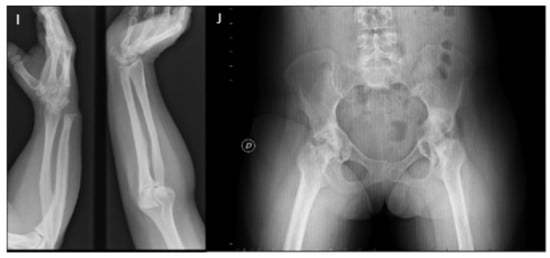

In 1993, the diagnosis worsened as the diseases progressed over time and deformities of the hands, feet, knees, hips and spine were present, accompanied by a considerable loss of strength (Figure 3).

Figure 3.

Radiologic controls. Phenotypic progression. (A) Radiological control hands in 2008. (B) Radiological control hands in 2011. (C) Radiological control hands in 2014. (D) Photography hands in 2021. (E) Serpentine fibula in 2002. (F) Photography legs in 2021. (G) Radiological control feet in 2014. (H) Photography feet in 2021. (I) Radiological control forearm in 2016. (J) Anteroposterior radiological control of the hip in 2013.